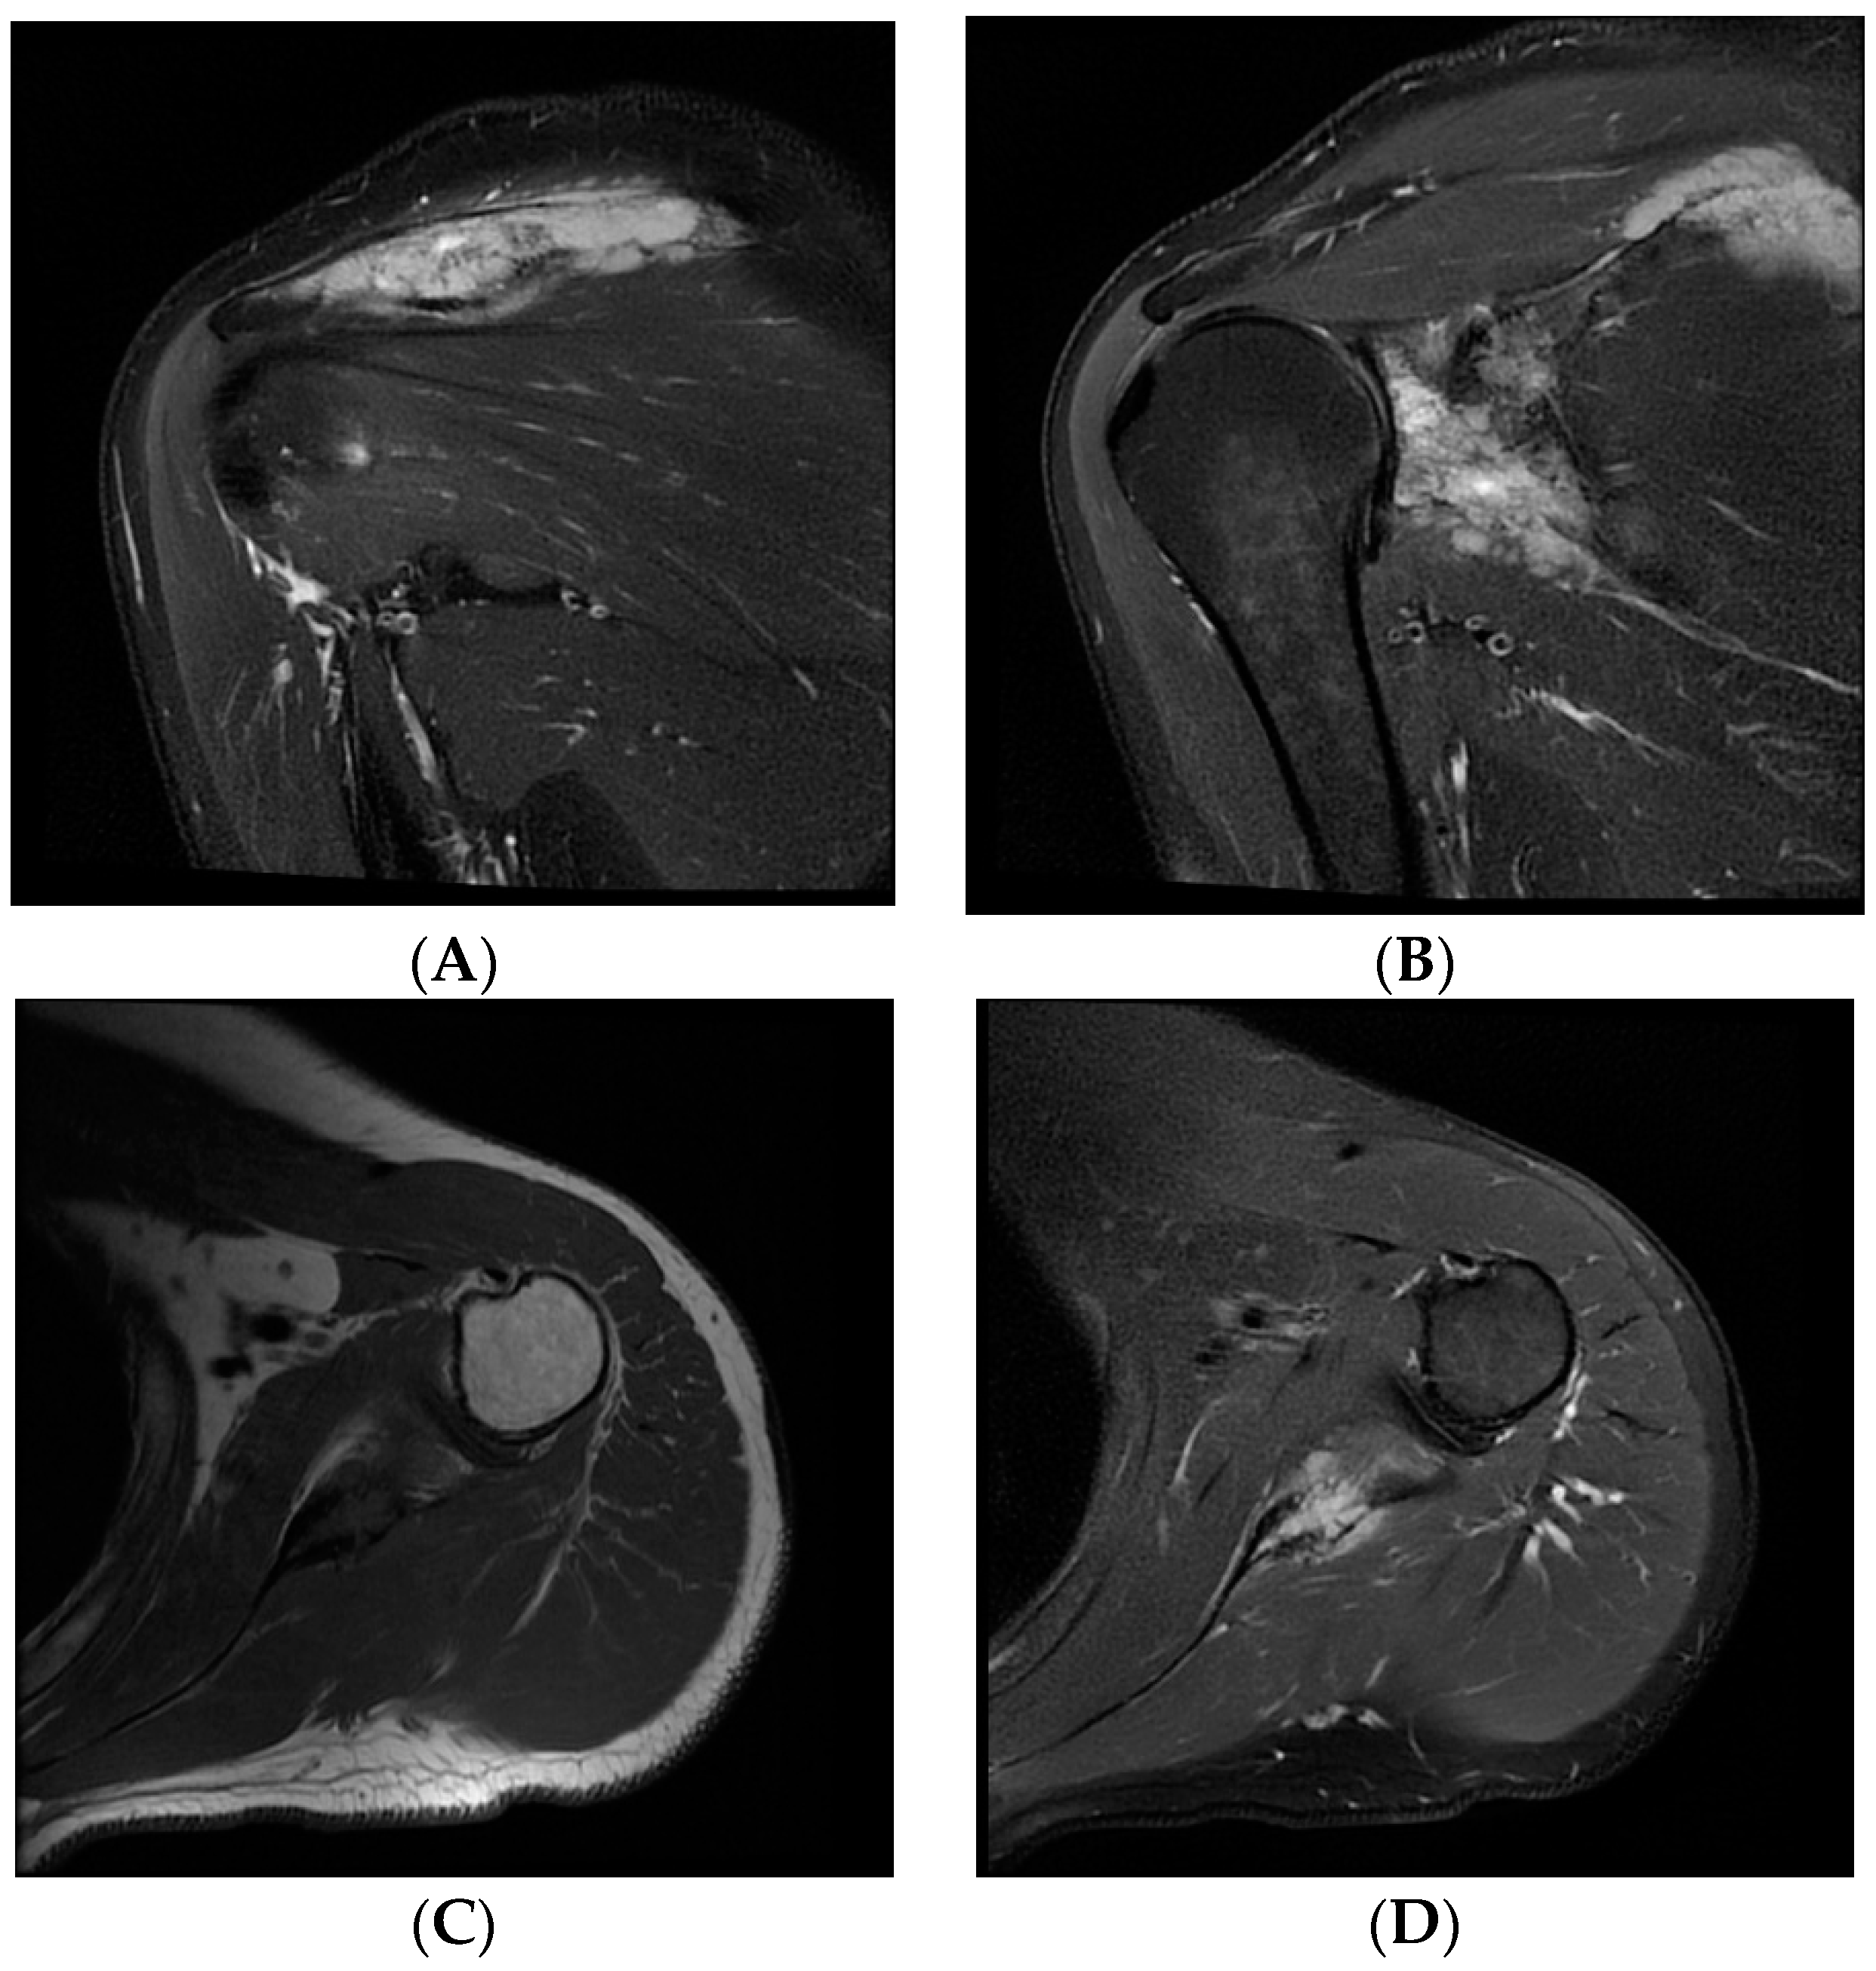

| Our patient | M/45y | Paresthesia, tingling, numbness and edema of the little and ring finger | Two years/ two years |

Surrounding soft tissue | R-CHOP chemotherapy + radiotherapy | Remission |